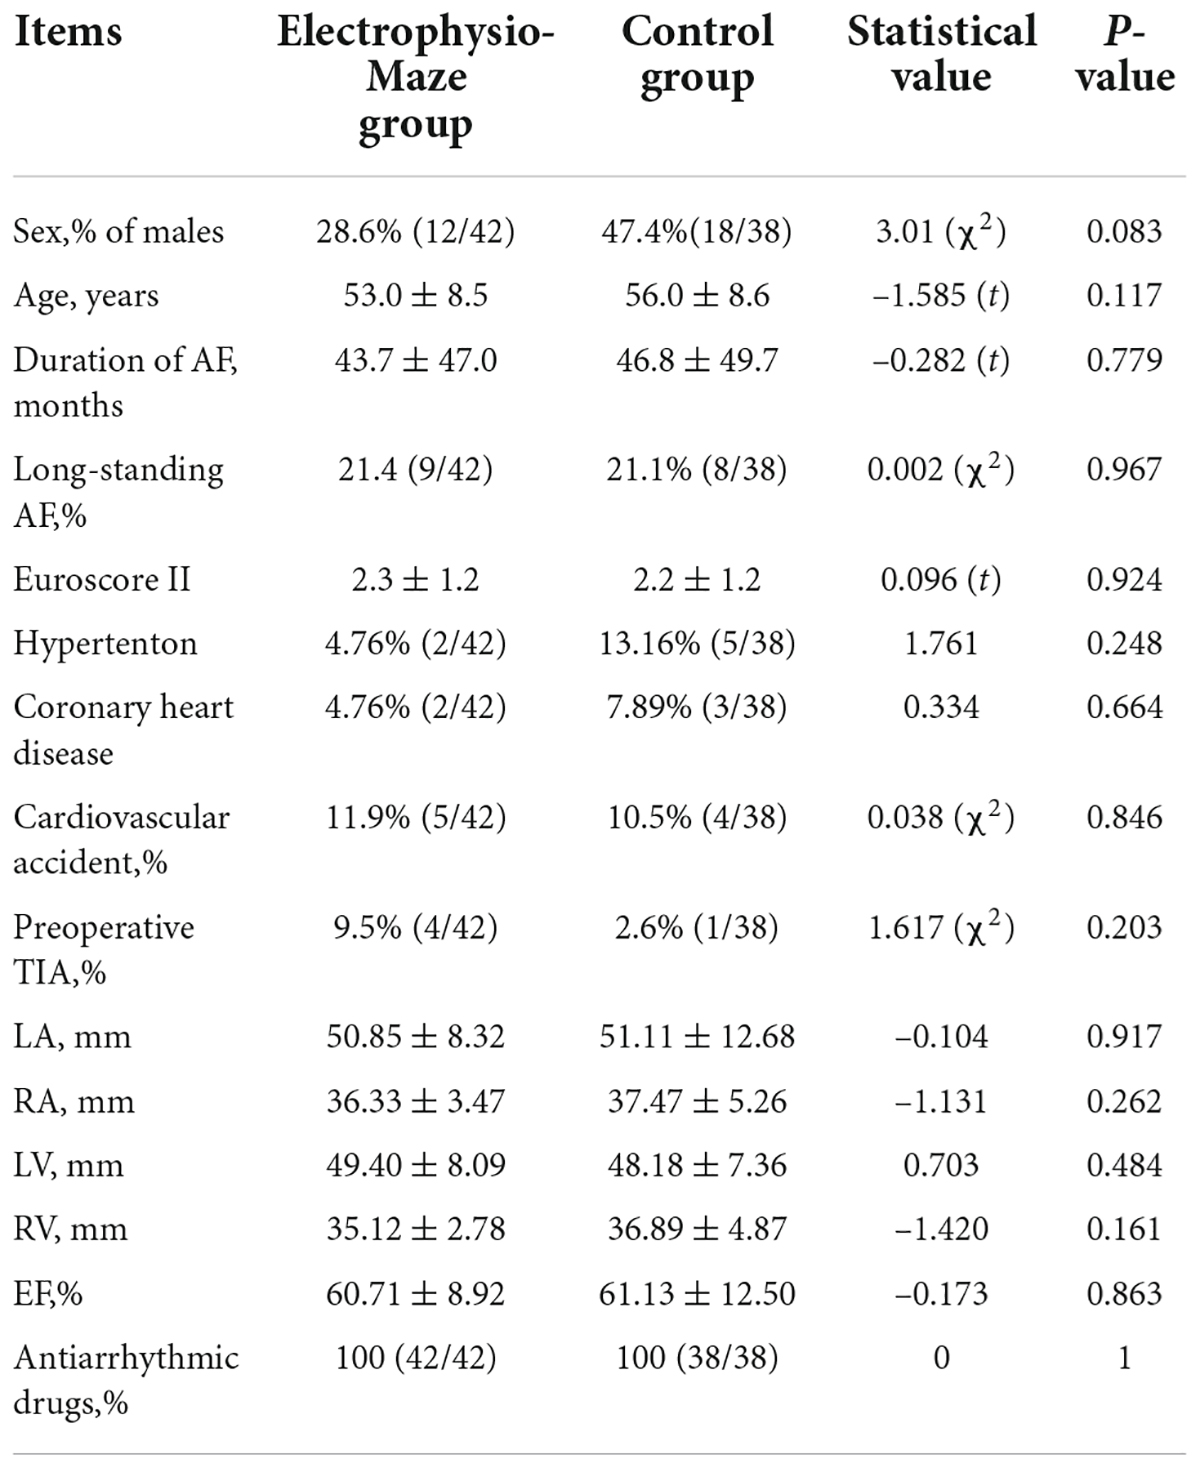

In the Electrophysio-Maze group, all patients underwent AF induction before and after the Cox-Maze IV procedure (Figure 1). The induction was performed with cannulization but without cardiopulmonary bypass, making the conditions consistent as much as possible. AF was induced in 88.1% (37/42) of all patients before Cox-Maze IV and was induced in 14.3% (6/42) of all patients after the Cox-Maze IV procedure. The bidirectional electrical isolation of the mitral annular isthmus ablation line (Figure 2), “box” ablation lines (Figure 3), and tricuspid annular ablation line (Figure 4) was successfully mapped in each patient. The rate of incomplete bidirectional electrical isolation of “box” ablation lines immediately after Cox-Maze IV was zero (the rate of complete bidirectional conduction block of “box” ablation lines immediately after Cox-Maze IV was 100%), and the rate of incomplete bidirectional electrical isolation of mitral isthmus ablation lines or tricuspid annulus ablation lines was 23.8% (10/42), wherein the rate of incomplete bidirectional electrical isolation of both mitral isthmus and tricuspid annulus ablation line was 7.14% (3/42), the rate of incomplete bi-directional electrical isolation of single mitral isthmus ablation line was 7.14% (3/42), and the rate of incomplete bidirectional electrical isolation of single tricuspid annulus ablation line was 9.52% (4/42). In two cases of incomplete bidirectional electrical isolation in single tricuspid annulus ablation line, complementary ablation was performed, and then electrophysiological mapping was performed again to ensure that the subsequent electrophysiological mapping confirmed the final complete bidirectional electrical isolation. The final incomplete bidirectional electrical isolation rate of mitral isthmus or tricuspid annulus ablation line was 19.0% (8/42). The incomplete bidirectional electrical isolation rate of ablation lines was correlated with AF inducibility immediately after Cox-Maze IV procedure but not with AF inducibility before Cox-Maze IV (Table 3).

Figure 1. Induction of atrial fibrillation (AF). (A) Image of programmed stimulation at high right atrial for induction of atrial fibrillation (post surgery). (B) AF induced by the 190 ms cycle stimulation before Cox-Maze IV. (C) After Cox-Maze IV, the 190 ms cycle stimulation failed to induce AF again. (D) After Cox-Maze IV, the 170 ms cycle stimulation could not induce AF; and (E) After Cox-Maze IV, the 150 ms cycle stimulation could not induce AF.